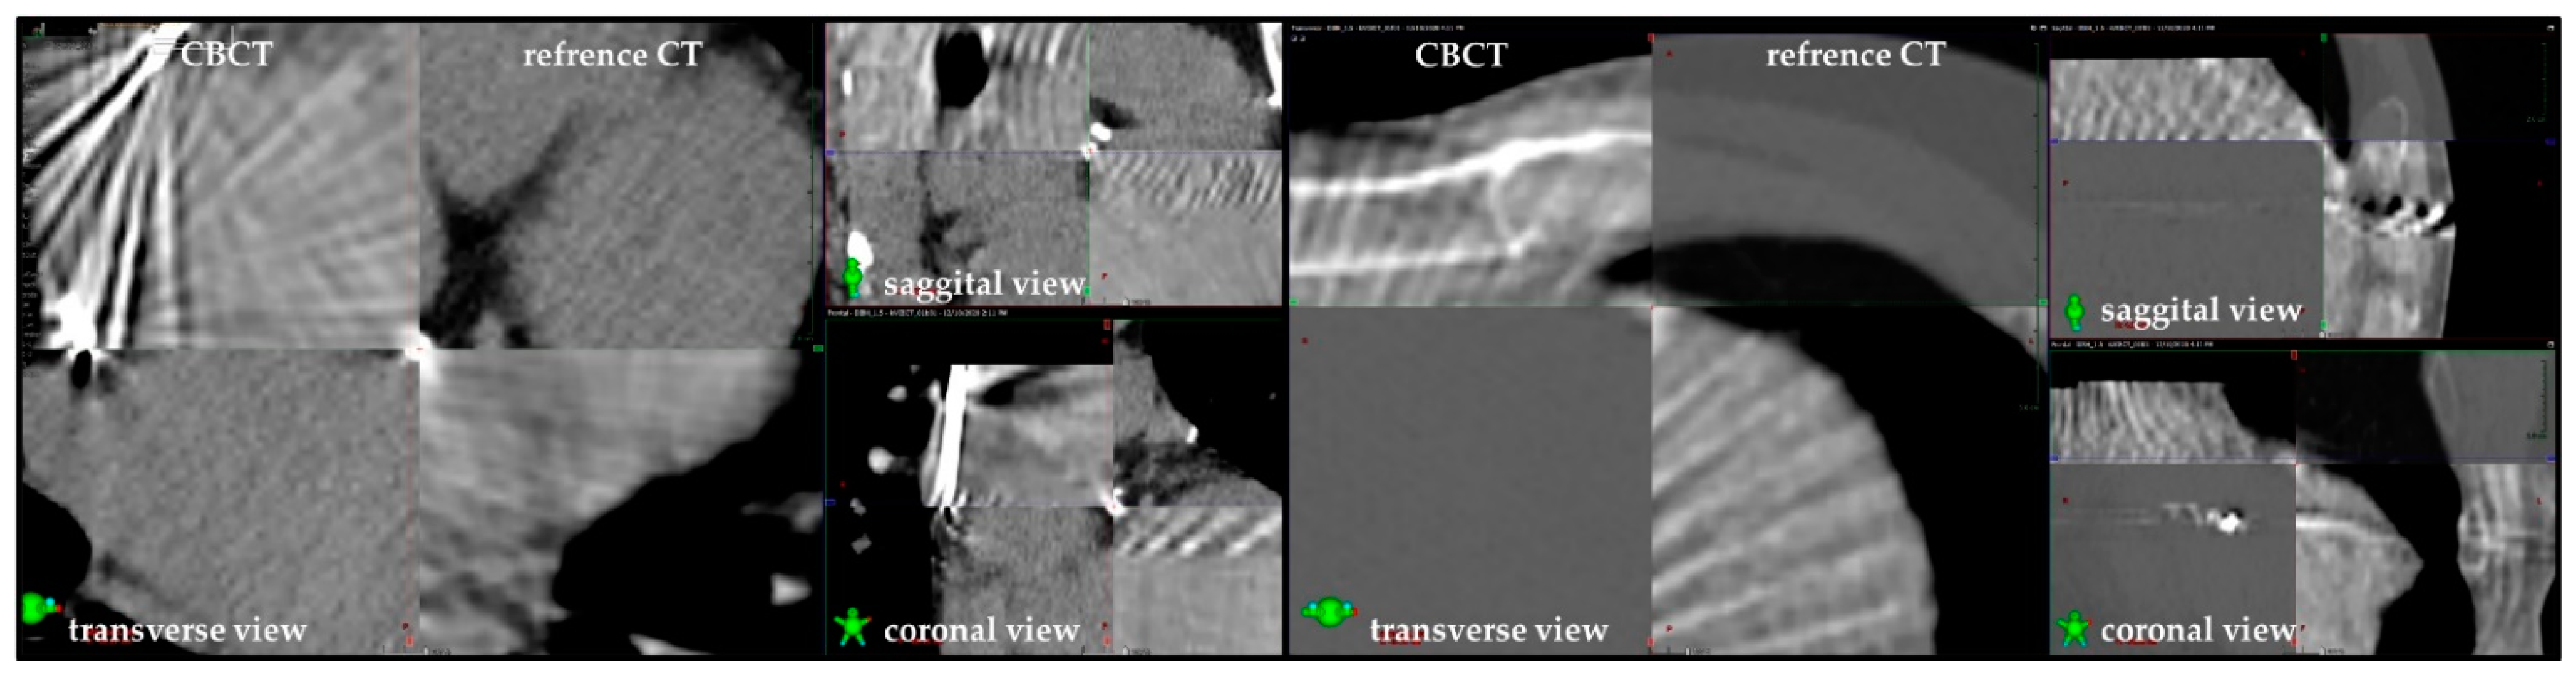

4.1. Target Volume Delineation